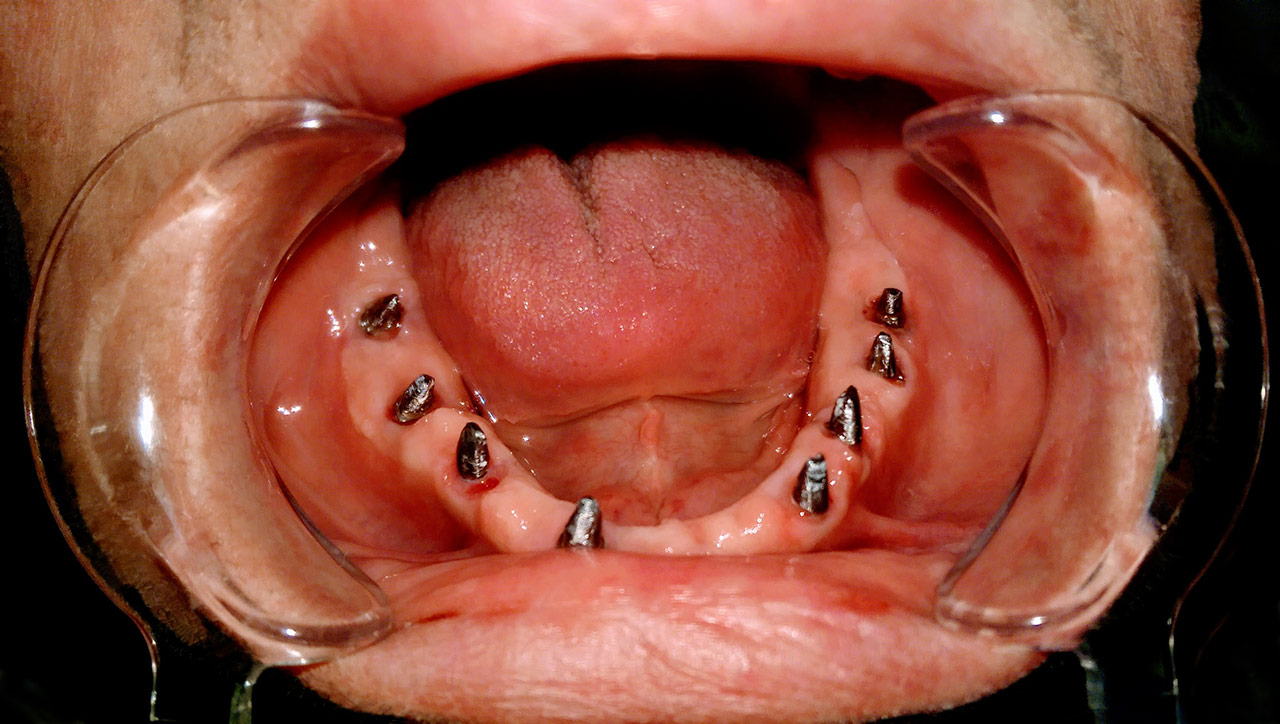

Alsó állcsont teljes rehabilitációja 72 óra alatt

Alsó állcsont teljes rehabilitációja 72 óra alatt, azonnal terhelhető implantátumokkal súlyos paradontitisben szenvedő dohányzó páciens esetében. Az alsó állcsont fogai mind mozogtak az előrehaladott fogágypusztulás miatt.

A fogakat eltávolítottuk, a gyulladt, fertőzött csontot kitakarítottuk, kifertőtlenítettük, majd azonnal implantáltunk.

Svájci, IHDE márkájú, azonnal terhelhető implantátumokat helyzetünk be, és ezekre harmadnapra rögzített, hosszútávú, fémvázas, esztétikus műanyaggal leplezett hidat ragasztottunk be.

Ezt az ideiglenes hidat a sebek gyógyulása miatt használjuk, de tartóssága miatt véglegesként is használható.

A legtöbb esetben, ahogy itt is, 6 hónap múlva porcelán hídra cseréljük, a teljes gyógyulás után.